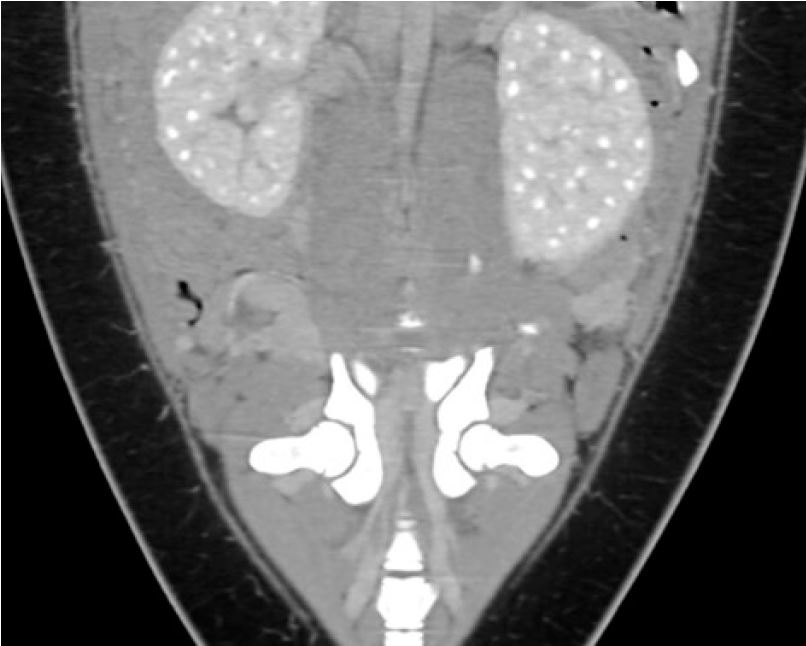

На комп’ютерній томографії всіх пацієнтів у паренхімі печінки виявлено велику порожнину, яка вбирає рідину. Цей висновок узгоджується з тонкостінним печінковим синусом, структурою, утвореною розширенням печінкових вен, що впадають у задню порожнисту вену. Тюлені також показали велику селезінку порівняно з собаками. Поєднання великої порожнини печінки та великої селезінки також зустрічається в інших пірнаючих ссавців.

Дослідники виявили, що у морських слонів існує кореляція між гематокритом і розміром порожнини печінки та селезінки на МРТ4. Вони виявили, що під час занурення у тюленя збільшувався гематокрит, а об'єм селезінки зменшувався. Одночасно збільшувався об'єм печінкового синуса. Очевидно, селезінка скорочується під час занурення, щоб проштовхнути еритроцити в кровообіг, щоб збільшити кількість кисню в крові. Додаткові еритроцити також з’являються в печінковому синусі, звідки вони доступні для циркуляції.

Малюнок 7: Аксіальні зображення живота Вінсента до і після контрастування показують велику заповнену рідиною порожнину в печінці, що відповідає печінковому синусу (GB — жовчний міхур).

Малюнок 9: корональний вид показує чітке поглинання контрасту обома нирками. Характерною є багатолопатева структура, яка виглядає як «білі крапки».